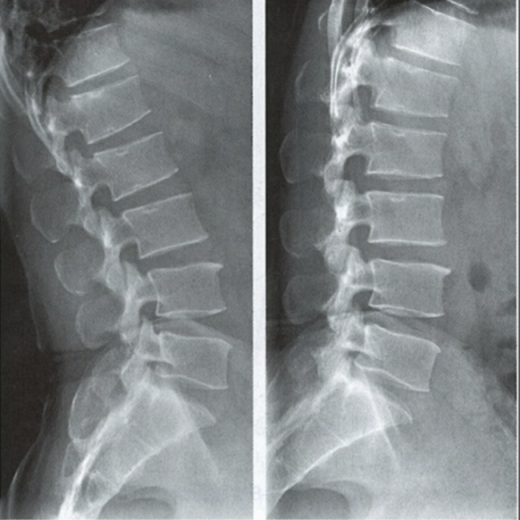

腰椎正側(cè)位

1. 上關(guān)節(jié)突;2. 下關(guān)節(jié)突;3. 椎弓根;4. 橫突;5. 椎體;6. 椎弓板;7. 椎間隙;8. 棘突;9. 椎間孔;10. 椎體上終板;11. 椎體下終板;12. 椎突間關(guān)節(jié)

腰椎動(dòng)力位 左圖為過(guò)伸位、右圖為過(guò)屈位